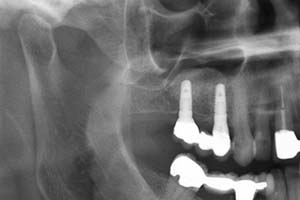

Ein weiterer oralchirurgischer Eingriff ist der sogenannte Knochenaufbau. Es bestehen viele Gründe wodurch ein Knochenaufbau, die sogenannte Knochenaugmentation, erforderlich werden kann. Eine fortgeschrittene Parodontitis kann zu Knochenrückgang in verschiedensten Bereichen des Kiefers führen. Die Knochenathrophie kann zudem auch durch Zysten im Kieferbereich erfolgen. Fehlende Zähne, die nicht durch Implantate ersetzt wurden, führen meist dazu, dass sich auch hier der Kieferknochen zurückbildet. Wenn herausnehmbare Prothesen schlecht und wackelig sitzen, kann der Vorgang des Kieferknochenabbaus noch verstärkt werden.

Knochenaufbauten oder sogenannte Kieferaugmentationen werden heutzutage sehr häufig durchgeführt. Von einfachen Maßnahmen nach einer Zahnextraktion zur Volumenstabilisierung bis hin zu komplexen Transplantationen körpereigenen Knochens führen wir bei uns in der Zahnärztlichen Praxisgemeinschaft Kampnagel verschiedenste Augmentationstechniken zum Kieferaufbau durch.

Bei einigen oralchirurgischen Operationen ist es in Sonderfällen möglich, dass kein eigenes Knochenmaterial verwendet werden kann, z.B. bei Sinusliftoperationen (Verbreiterung des Oberkiefers im Bereich der Kieferhöhle) oder bei einer Kieferkammverbreiterung. Hier versuchen wir stets als Alternative künstliches Knochenersatzmaterial zu verwenden um Ihnen ein zweites Operationsgebiet zu ersparen. Unter Umständen werden Membranen zur Fixierung des Augmentats benötigt.